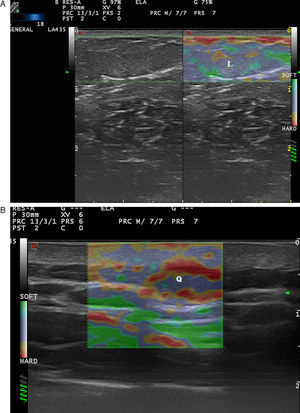

Lymph nodes have an elastic structure in which the cortex tends to be less rigid than the capsule and the hilum (Fig. 6).

To assess the stiffness of lymph nodes, SE is used to classify nodes in 4 or 5 categories according to the proportion of stiff areas they present.31 Benign enlarged nodes generally tend to be soft, whereas malignant nodes tend to be stiffer.32 However, lymphomas are less stiff than metastatic nodes and similar in stiffness to inflamed nodes. Therefore, benign and lymphomatous nodes cannot be distinguished with elastography alone.33

In the case of melanoma (Fig. 7), Hinz et al.34 found that elastography in addition to conventional B-mode sonography combined with color Doppler sonography increased sensitivity in the detection of metastatic disease in clinically suspicious enlarged lymph nodes from 80.9% to 95.2% but found no increase in specificity (76.2%). Similar results were obtained in later studies such as that of Ogata et al.35